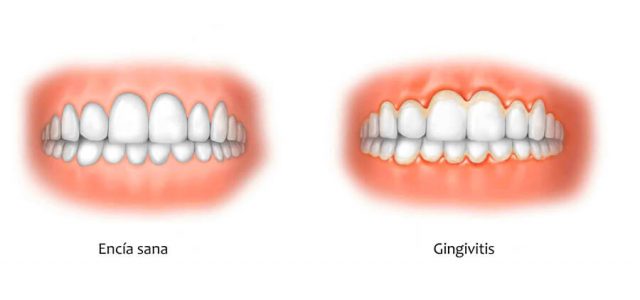

Gingivitis

Consiste en la inflamación de la encía alrededor del diente por la acumulación de restos alimenticios o placa dental.

Debido a una mala higiene bucal, esta placa, que está compuesta de bacterias y depósitos calcáreos, se va acumulando en nuestra cavidad oral hasta formar lo que comúnmente conocemos como sarro.

Una vez que las bacterias se han agrupado crean cálculos dentales, ya solo pueden ser eliminadas por un profesional mediante una limpieza dental o profilaxis.

Con el paso del tiempo hacen que la encía se debilite y sea más propensa a sufrir pérdida de hueso y sangrado, que ocasionen la recesión de las encías.

La gingivitis es una enfermedad muy frecuente entre los adultos y afecta al 91% de la población.

Su principal síntoma es el sangrado de la encía durante el cepillado. Una encía sana no debería sangrar nunca durante el mismo.

Cabe mencionar que, en los pacientes fumadores, este signo se enmascara y es muy poco probable que sangren sus encías aunque sufran la enfermedad.

Por ello, recomendamos que acudas regularmente a revisión para que te examine un periodoncista (odontólogo especializado en patologías periodontales).